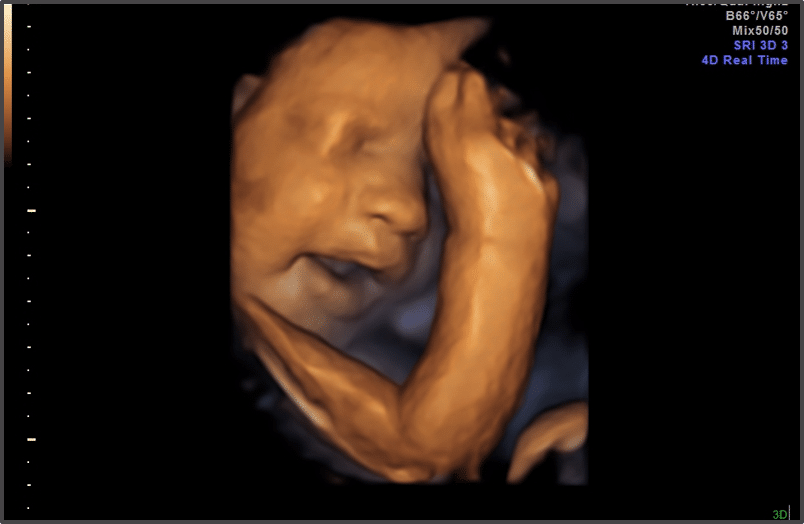

Ултразвук

(31 гестационна седмица)

През 31 гестационна седмица вашият плод преминава през основно развитие на мозъка и нервната система. Очите му също се развиват – ирисите вече могат да реагират на светлина! Всъщност, всичките пет сетива на бебето са в изправност.

Бременност 31 гестационна седмица ултразвук Източник: https://www.thebirthcompany.co.uk/

Жените, които имат усложнения по време на бременността, като гестационен диабет или които са бременни с близнаци, е възможно да посещават АГ по-често от обикновено. Някои любопитни родители избират да направят 3D / 4D ултразвук в края на временността – обикновено някъде между и (така че 31-вата седмица от бременността е идеалното време!)

При 3D / 4D ултразвук можете да видите оформеното личице на вашето бебе и как извършва елементарни движения. Това означава, че може да видите вашия 31-седмичен плод да мига, да смуче палец, а може би дори да се усмихва или да се намръщи.